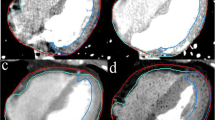

GTV delineation, volume and displacement determination

All of the 4DCT data sets of each patient were registered to the reference 4DCT scanning (the first 4DCT scan/simulation) corresponding to the end expiration phase (respiratory phase 50%, GTV50) using software tools in the radiation treatment-planning system on the basis of bony landmarks for comparison. For each 4DCT data set, the primary tumor (was considered as the GTV) was drawn by a single physician with same window level and window widths. The full respiration GTV centroid positions were acquired by the Varian Eclipse 8.6 treatment planning system. Volumes were constructed using three approaches: GTVmean was the average of all 10 phases of each GTV, IGTVMIP was the contour delineated from the MIP, all 10 GTVs were combined to form IGTV10. Displacement in each direction between the center of the GTV50 contour on the simulation scan and the centers on subsequent scans was used to assess interfraction displacement between fractions, which was obtained by coordinates of the GTV50 centroid on the subsequent datasets subtracted that on the reference dataset. In addition, the three dimensional tumor motion vector was obtained using motion data in the different axes.